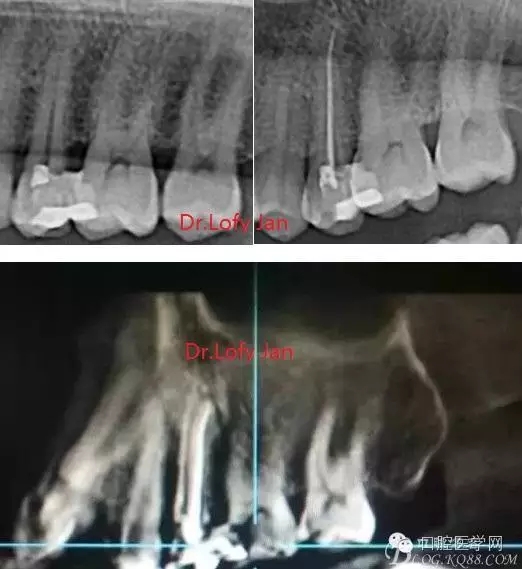

前言:自己做的一些曲面斷層片在未試尖根管治療中的病例整理,發(fā)現(xiàn)問題很多包括自身的,技術(shù)的,還有設(shè)備的問題,予以總結(jié)整理并期待進(jìn)一步提高。

根管治療術(shù)是牙體牙髓疾病治療中最復(fù)雜和最關(guān)鍵的治療項(xiàng)目。根管充填材料抵達(dá)根尖、并能嚴(yán)密堵塞根尖孔,是確保根管治療效果的關(guān)鍵指標(biāo)。為了保證根管充填到位,醫(yī)生需要在術(shù)前照牙片以了解牙根根管的數(shù)量、彎曲程度和長度,在術(shù)中有時(shí)需要插針照牙片來精確測量根管長度,術(shù)后必須照牙片以確定是否根管充填到位,如果欠填或超填,就需要重新充填、重新照牙片確認(rèn),直到根管充填到位。所以,在患者接受根管治療時(shí)有時(shí)會反復(fù)照牙片。

《數(shù)字化根尖片、曲面斷層片、CBCT測量牙齒長度準(zhǔn)確性的比較研究》文中顯示:平行投照數(shù)字化根尖片影像長度和牙齒實(shí)際長度之間無顯著性差異(P0.05);數(shù)字化曲面斷層片影像長度和牙齒實(shí)際長度之間有顯著性差異(P0.05),平均失真率為17.05%。CBCT冠狀面測量結(jié)果中除上頜前磨牙區(qū)、下頜前磨牙區(qū)與真實(shí)長度差異無統(tǒng)計(jì)學(xué)意義(P0.05)外,其余6個(gè)分區(qū)差異均有統(tǒng)計(jì)學(xué)意義(P0.05);矢狀面測量結(jié)果中上頜磨牙區(qū)、下頜磨牙區(qū)、下頜前磨牙區(qū)、下頜尖牙區(qū)、下頜前牙區(qū)與真實(shí)長度比較差異均有統(tǒng)計(jì)學(xué)意義(P0.05)。結(jié)論平行投照數(shù)字化根尖片較曲面斷層片和CBCT能更加精確地反映牙齒的真實(shí)長度。

病例分析:曲面斷層片在x線輔助診斷與檢查中目前大多數(shù)文獻(xiàn)和著作都建議只能作為初診拍片檢查手段,不能作為終末疾病的確診與手術(shù)療效的評價(jià)指標(biāo),臨床大部分中小型門診都因?yàn)樵O(shè)備不齊全導(dǎo)致信息偏差很大。